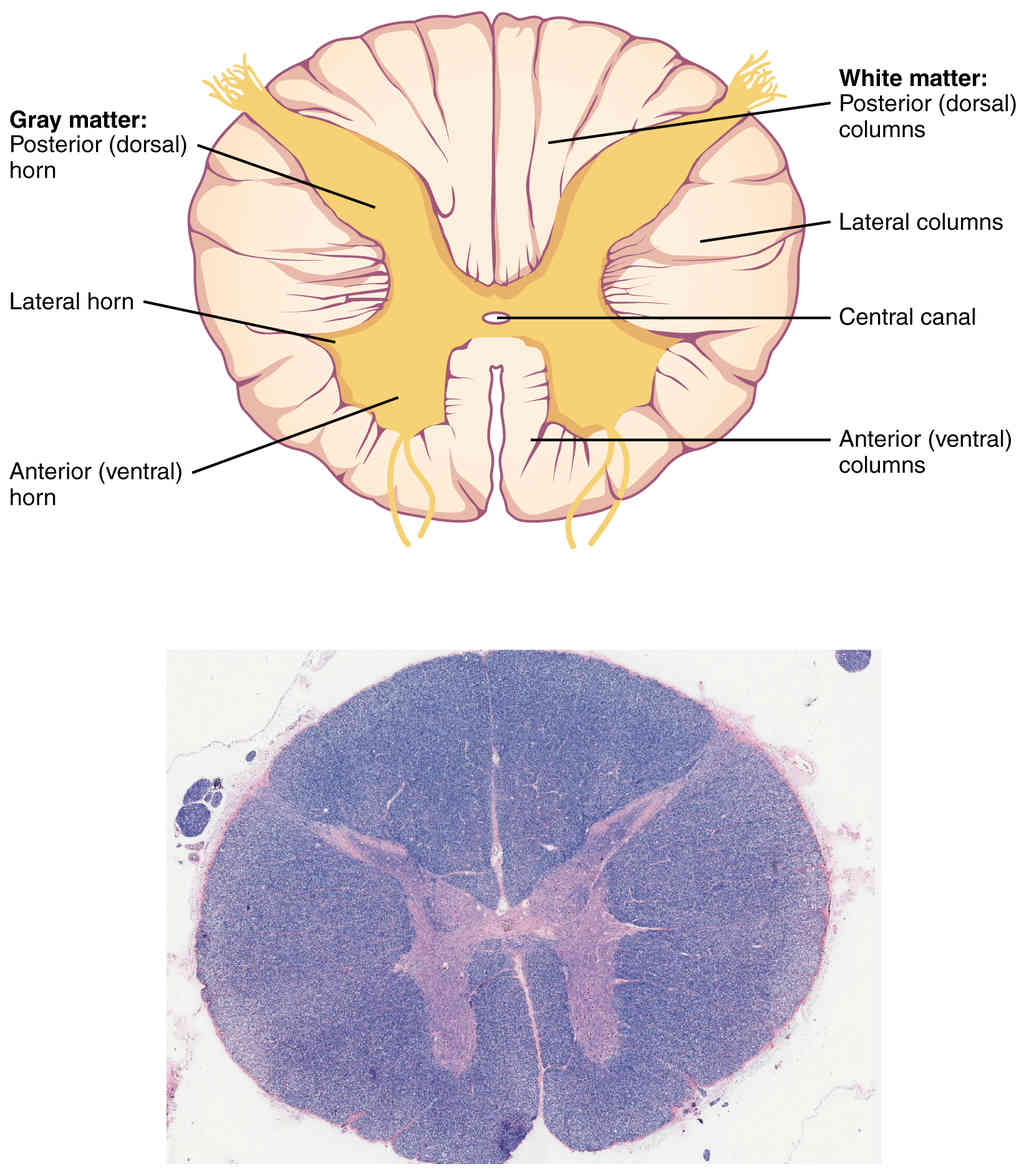

This page is under construction. For now, it is just a resource of the images found in the OpenStax Anatomy and Physiology Handbook. It wil slowly change into a revision tool. Each slide has a number. Use this to refer to the slide. When completed, it will have an unlabelled section, with labelled slides in parallel. On the unlabelled slides, write your answer and use the labelled slide to assess yourself. Keep track by also noting the number on each slide. Improvement at each attempt is important, more so than full marks on a first attempt.